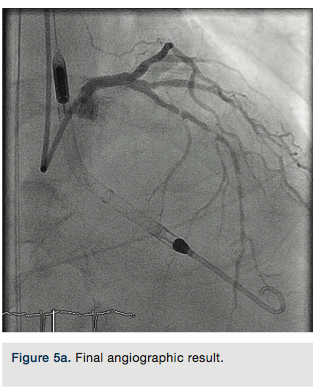

LAD guide wire was withdrawn and the LAD was rewired through the LM portion of the stent. A 3.5 x 15mm Sprinter balloon (Medtronic) was used to cross into the LAD and inflated at 18atm. A 3.5 x 12mm Resolute Integrity stent was deployed at the proximal LAD into the LM at 18atm. The LCX guide wire was pulled back into the guide catheter, and re-advanced into the LCX through the LM stent. Two 3.5 x 15mm NC Sprinter balloons were placed from the LM to the LCX and LAD, and a simultaneous “kissing” inflation was performed at 14atm (Figure 4). A 4.0 x 12mm NC Sprinter balloon was inflated in the LM portion of the stents at 18atm for proximal optimization. IVUS examination revealed excellent stent apposition (Figures 5a-5b). The stenoses in the proximal, mid and distal LAD were not treated. All catheters were removed except the Impella catheter, which was anchored in place using sutures.